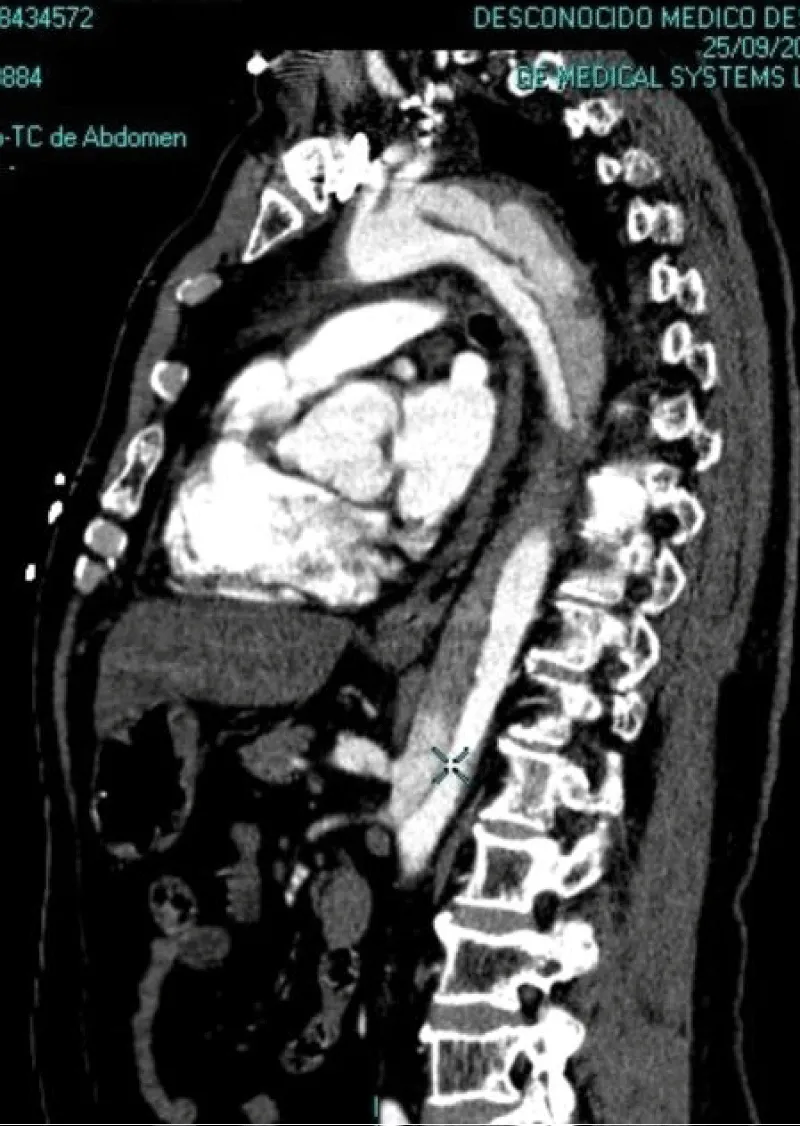

No acute ST-T abnormalities with biomarkers (troponin T and CK) repeatedly in the normal range. Normal blood count and coagulation studies. The patient is then admitted to the ICU. In the clinic of chest pain with negative electrical and enzymatic data, a CT scan is performed with intravenous contrast then unfold the existence of acute aortic syndrome Stanford type B (Figure 2). Transthoracic echocardiography was performed, showing preserved systolic function, without contractility alterations, without valvular disease but with slight left ventricular hypertrophy and slight pericardial effusion, with intimal flap distal to the left subclavian artery in the suprasternal plane.

Download Image

Figure 2: Lateral CT image where it can be an observed dissection of the aortic artery, with false lumen distal to left subclavian artery to the abdominal aorta without affecting the aortic arch (Stanford type B).